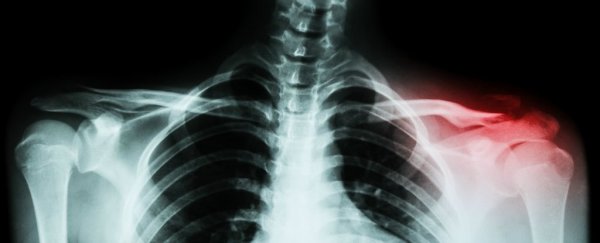

新的技术抛弃了使用外源细胞或者分子来做修补和让受损骨骼组织重新生长,而是使用了聚合物纳米壳,一种放置于体内的微型胶囊,可以把微小RNA分子送到损伤处。当纳米壳开始分解时,微小RNA分子就被释放出来,指挥周围的细胞“激活”天然的造骨和愈合机制。有点像项目经理在拆迁现场,指挥建筑工人重建房屋一样。

这个新技术有两点关键优势。一、纳米壳是设计为缓慢分解的,这样可以逐渐释放微小RNA分子,因此恢复性治疗可以触须一个月或者更久。二、这个过程使用人类自己的细胞,而不是引入外源修复中介,就避免了细胞排斥或者跟损伤有关的肿瘤。

这很重要,因为理论上说,我们的骨头本身就含有一切可以保持健康强壮的成分,但是愈合过程却并非在需要的时候可以激活,因此才会有持续损伤,蛀牙或者骨质疏松。把管理愈合过程的任务交给微小RNA,研究者们希望修复工作可以做到持续和彻底。

虽然这项技术只在老鼠身上试验过,但它很有希望对人类也有用,这也是研究者下一步的打算。最终,这种自愈治疗将会用来等待骨科手术或者关节修复,甚至龋齿修复(Ma自己就是一名牙医学教授)。

在专门目的下生长和再生高质量的骨骼一直是个充满挑战的难题,因此密歇根大学的新发现充满了潜力。实验中使用的老鼠患有骨质疏松,在欧洲,美国和日本有近7500万骨质疏松患者,这些人的生活将会因为这项技术得到改善。